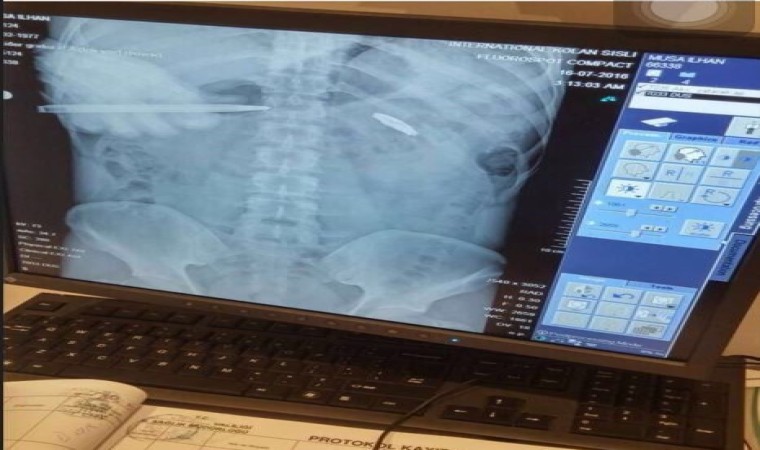

15 Temmuz darbe girişimi esnasında demokrasiye sahip çıkmak için sokağa çıkan Musa İlhan, hainlerin sıktığı kurşunla kalbinin 2 milimetre altından yaralandı. Kurşunun vücudundan çıkarılmasının riskli olması nedeniyle 8 yıldır hainlerin sıktığı mermiyle yaşayan İlhan, “Rabbim gaziliğin ecrini ahirette, gururunu da bu dünyada yaşamayı nasip etsin. 8 yıl oldu kurşun vücudumun bir parçası. Bunu ahiret nişanesi olarak taşıyorum. Bazı sağlık sorunlarına sebep olsa da bu benim gururum, nişanem, madalyam. Allah tekrar böyle acı olayları bize yaşatmasın. Bizler Türk milletiyiz, asla vatansız yaşayamayız” dedi.

Fetullahçı Terör Örgütü’nün (FETÖ) 15 Temmuz 2016 tarihinde gerçekleştirdiği hain darbe girişiminin üzerinden 8 yıl geçti. Darbe girişiminde her yaştan vatandaş sokağa çıkarak darbeye ‘dur’ dedi. O vatandaşlardan kimi şehit oldu kimi de yaralanarak gazilik mertebesine erişti. Demokrasiye sahip çıkmak için sokağa çıkan Musa İlhan da darbeye karşı duranlardandı. İlhan, trafikte seyir halindeyken 15 Temmuz hain darbe girişimini radyodan öğrendi. Vatan savunması için sokakta kalan Musa İlhan, korkusuz bir şekilde darbeci askerlerin karşısına dikildi. Darbecilerin kurşunlarının hedefi olan İlhan, kalbinin 2 milimetre altına isabet eden mermiyle yere yığıldı. Ağır yaralanan İlhan, çevredekiler tarafından hastaneye kaldırıldı. 4 gün yoğun bakımda kalan İlhan, 2 ay süren tedavinin ardından sağlığına kavuştu. Ancak cerrahi müdahale riskli olduğu için kurşun çıkarılamazken, 8 yıldır hainlerin sıktığı mermiyle yaşıyor.

Afet Koordinasyon Merkezi’nin işgal edildiğini öğrenince oraya yöneldiğini ifade eden İlhan, “Girer girmez ayaklarımıza doğru bir ateş açıldı. Tabii önce bir korktuk çünkü ateş açılmasını beklemiyorduk. Yanımda hocam vardı. Sonra o bahsetti. ‘O kadar gözün dönmüştü ki ne yaptığını bilmiyordun’ dedi. Asker bana, ‘gelme vururum’ diye bağırıyormuş. Ben de, ‘geleceğim vuracaksan vur’ diyormuşum. Vurulduğumu hatırlıyorum. Kurşun göğsüme geldi. 10-15 dakika boyunca yerde yattım. Arkadaşlardan birisi tampon yaptı. Bir yandan da omzumun kenarından kendini saklıyordu. Çünkü sürekli ateş ediliyordu. AKOM’un çatısına makineli tüfek kurulmuştu. Ölüm insanın aklına geliyor. Kanın aktığını hissettim. Benim için ‘öldü’ dediklerini duydum. O an aklıma ‘Allah bize şehitliği nasip edecek’ diye düşündüm. 6-7 ay önce Hacca gittiğimde, hoca demişti ki; ‘Kabe’yi gördüğünüzde aklınıza ne dua geliyorsa onu edin.’ Kol kola girdik, gözlerimiz kapalı ama heyecandan aklıma dua gelmedi. O an, ‘Rabbim bana şehitliği nasip eyle’ demiştim. Onlar aklıma geliyordu. Sonrasında beni yoğun bakıma kaldırmışlar. Uyandığımda tabii hiçbir şeyden haberim yok. Hemşireye, ‘Cumhurbaşkanı yaşıyor mu’ diye sordum. O da bana yaşadığını ve doktorların bir araya gelse kurşunu oraya koymalarının imkansız olduğunu söyledi. Kurşun kalbimin 2 milimetre altında kalmış. 2 milimetre yukarı gelse kalbime isabet edecekti. Sonra rahat bir nefes aldım ve ülke selamete ermiş dedim. 2 ay boyunca tedavim evde devam etti. 4 gün yoğun bakımda kaldım. Sonrasında evde istirahat ettim. Hamd olsun. Rabbim gaziliğin ecrini ahirette, gururunu da bu dünyada yaşamayı nasip etsin. 8 yıl oldu kurşun vücudumun bir parçası. Bunu ahiret nişanesi olarak taşıyorum. Belki ahirete götüreceğim. Bazı sağlık sorunlarıma sebep olsa da bu benim gururum, nişanem, madalyam. Allah tekrar böyle acı olayları bize yaşatmasın. Bizler Türk milletiyiz, asla vatansız yaşayamayız. Bizler 105 yıl önce Çanakkale’de 250 bin şehit vermişken 2016 yılında 15 Temmuz’da 252 tane şehit verdik. Sayı önemli değil. Bizler ne olursa olsun, vatanımızı asla böldürmeyiz. Allah kimseye böyle durumlar yaşatmasın. Vatan demek, namus demek. Vatan demek, bayrak demek. Vatan demek, can demek. Namusumuza da, bayrağımıza da, vatanımıza da sahip çıktığımızı düşünüyorum” şeklinde konuştu.